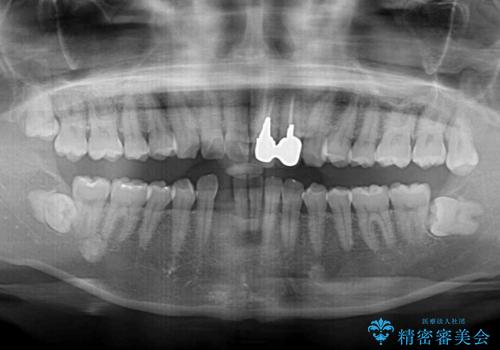

- 下顎前歯が抜けそうとのことで来院された患者様です。

初診の状態ではすぐにでも抜けそうな状態で、インプラントによる補綴治療を行うこととしました。

インプラント治療に際し、前歯の叢生に対する矯正治療を提案したところ、興味を持たれたので、インビザライン・ライトによる矯正治療を行うこととしました。

抜歯後にスペースができると恥ずかしいため、抜歯した歯を接着剤で固定した上で矯正治療を行い、その後インプラントやオールセラミッククラウンの装着を行うこととしました。